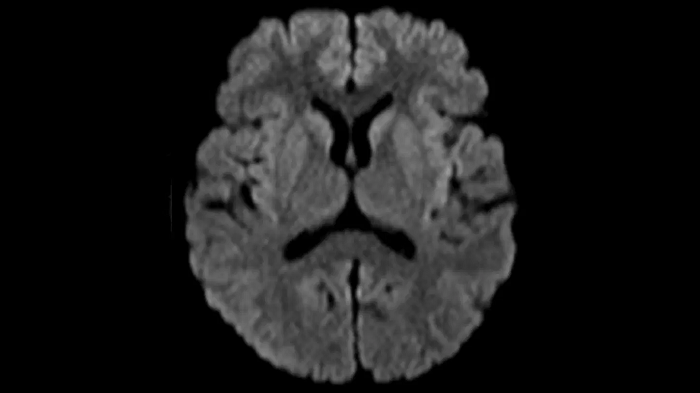

DWI b1000

Exceptional diffusion-weighted imaging with MAGNETOM Free.Star.

PAT 2

0.7 x 0.7 x 5.0 mm2

TA 2:53 minutes

MAC-ID: 7aaaa0195. Image Credit: Siemens Healthineers